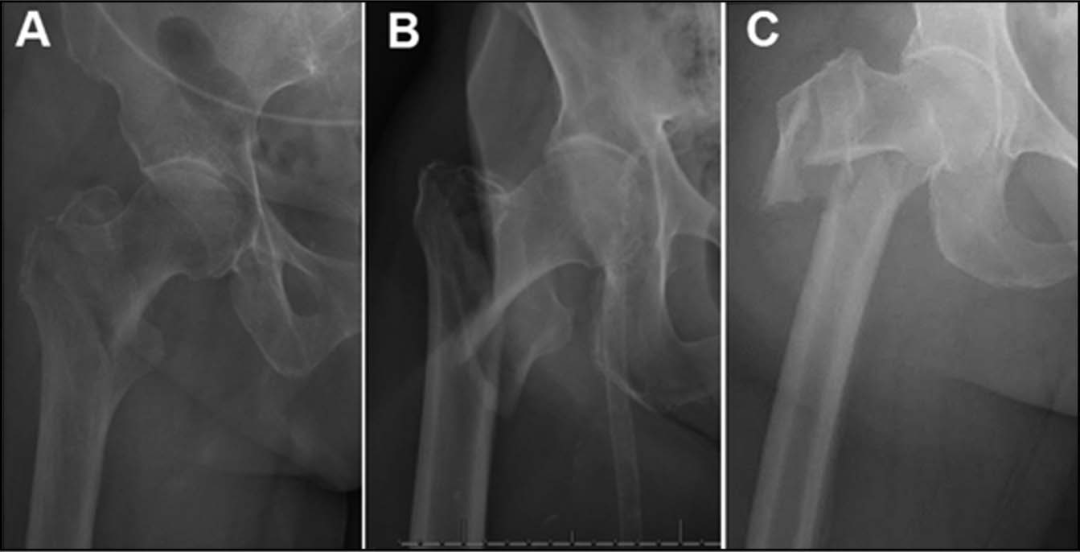

在任何粗隆间骨折类型中,中长度钉都可以作为短钉的替代品。绝对指征:低转子间骨折,延伸超过3cm远端至小转子底部存在远端柄植入物,如柄膝关节置换术(图)。

存在无法移除或不打算移除的远端股钢板(图)。

考虑到远端骨折延伸,使用短钉是不合适的,而由于远端髓内植入物的存在,不能使用长钉。

外侧壁骨折的存在是骨折内翻塌陷的潜在危险因素,特别是对于股骨髓腔较大的患者,在这些骨折中,较长的钉可能是首选(图)。